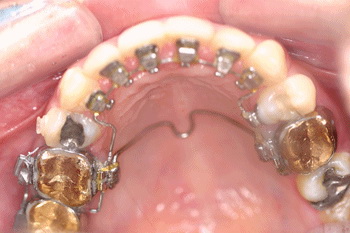

설측교정치료란, 기존에 치아교정장치를 입술 쪽에 붙이는 것과는 달리 치아의 설측면, 즉 입천장쪽이나 혀쪽으로 장치를 붙여서 하는 치아교정치료술이다. 밖에서 안 보이는 치아 뒤쪽에 장치를 붙이므로 치아교정장치가 보이지 않아 타인에게 본인이 치아교정치료를 한다는 것을 숨길 수 있어 비밀교정이라고 불리기도 한다.

하지만 장치를 설측으로 붙이면서 기존의 치아교정방법과 달리 기술적으로 신경써야하는 부분들이 많다. 일단 치아는 순측에 비해 설측의 구조가 훨씬 복잡하다. 게다가 순측에 비해 설측에 장치를 붙일 때는 시야확보가 어렵다. 이러한 이유 때문에 설측교정의 경우는 교정장치의 접착 위치를 복제된 치아모형상에서 미리 설정해서 접착하는 간접접착방법을 사용한다. 간접접착방법을 사용하면 치료 후의 치아위치를 예상해서 보다 정확하게 교정장치를 장착할 수 있다.

<사진>설측교정장치(위)와 간접접착방법.